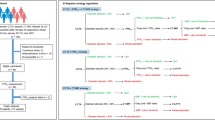

Fractional flow reserve derived from coronary CT (FFR-CT) is a noninvasive physiological technique that has shown a good correlation with invasive FFR. However, the use of FFR-CT is restricted by strict application standards, and the diagnostic accuracy of FFR-CT analysis may potentially be decreased by severely calcified coronary arteries because of blooming and beam hardening artifacts. The aim of this study was to evaluate the utility of deep learning (DL)-based coronary computed tomography (CT) data analysis in predicting invasive fractional flow reserve (FFR), especially in cases with severely calcified coronary arteries. We analyzed 184 consecutive cases (241 coronary arteries) which underwent coronary CT and invasive coronary angiography, including invasive FFR, within a three-month period. Mean coronary artery calcium scores were 963 ± 1226. We evaluated and compared the vessel-based diagnostic accuracy of our proposed DL model and a visual assessment to evaluate functionally significant coronary artery stenosis (invasive FFR < 0.80). A deep neural network was trained with consecutive short axial images of coronary arteries on coronary CT. Ninety-one coronary arteries of 89 cases (48%) had FFR-positive functionally significant stenosis. On receiver operating characteristics (ROC) analysis to predict FFR-positive stenosis using the trained DL model, average area under the curve (AUC) of the ROC curve was 0.756, which was superior to the AUC of visual assessment of significant (≥ 70%) coronary artery stenosis on CT (0.574, P = 0.011). The sensitivity, specificity, positive and negative predictive value (PPV and NPV), and accuracy of the DL model and visual assessment for detecting FFR-positive stenosis were 82 and 36%, 68 and 78%, 59 and 48%, 87 and 69%, and 73 and 63%, respectively. Sensitivity and NPV for the prediction of FFR-positive stenosis were significantly higher with our DL model than visual assessment (P = 0.0004, and P = 0.024). DL-based coronary CT data analysis has a higher diagnostic accuracy for functionally significant coronary artery stenosis than visual assessment.